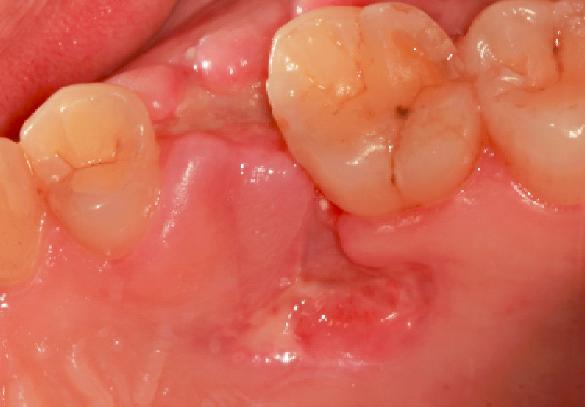

拔牙后的"血窟窿"一词其实是形象化了,听着吓人,在医学上成为牙床,它是可以愈合的,只是需要时间。愈合的过程也是牙齿组织再生的过程。

拔牙后的15分钟:血液凝块凝结

医生在拔除牙齿之后的15分钟,牙齿创口中血液会迅速聚集在伤口处凝结成血块就像平时我们身体其他地方磕碰流血的道理一样,血块凝结覆盖牙槽窝只是发自人体本能保护伤口形成保护膜,预防细菌侵袭感染。而为了促进凝血块的形成,这时,医生一般会让患者咬着棉花球30至40分钟。

24小时后:组织纤维"驻扎"血凝块

当血凝块产生之后,组织纤维开始慢慢"驻扎"进血凝块之中形成血凝块有机化,这是为了更好的保护牙齿预防细菌感染,在24小时之内不可以漱口、吸烟、喝酒。此时牙槽内部依然处于脆弱的阶段,稍加不注意,就会使血凝块脱落,引发牙槽二次出血的状况。

3天至5天后:上皮组织逐渐覆盖牙窝

血凝块有机化后,经过时间的推移,会逐渐转化为肉芽组织,同时牙龈上皮也开始由周围像血凝块表面生长,逐渐覆盖整个创伤表面,这个过程大概需要7天左右,但要全部长好,正常情况下需要一个月。

7天之后骨组织开始重生

拔牙后的每一天创口都在变化,而在第7天后,牙槽窝的新骨逐渐形成,然而新骨从重建到完成则需要3个月至6个月形成。这时的伤口基本愈合。